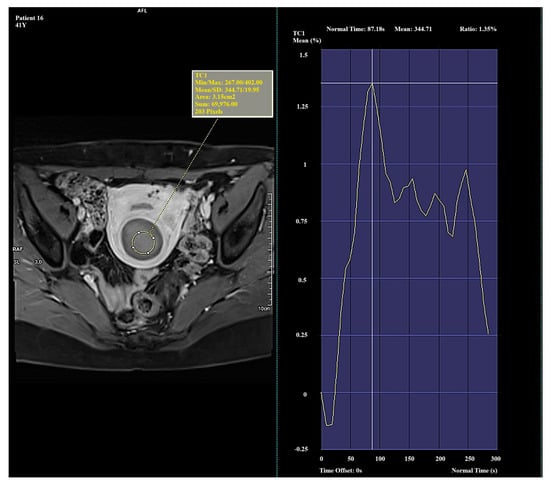

It was noted that Type III myomas occurred only in older patients (mean age, 54.8 years), suggesting a potential relationship between age and reduced vascularization. This may indicate the age-related degeneration of myomas, which could influence their responsiveness to treatments such as HIFU, RFA, or embolization. Type III lesions, characterized by weaker vascularization, may be less responsive to these therapeutic methods, which are most effective for highly vascularized lesions. Due to the small sample size and reduced susceptibility to treatment with HIFU, RFA, or embolization, this group was excluded from further analysis.

In Type I, the average Ratio was 156.96 ± 20.94 (Me = 156.89), the average TTP was 127.04 ± 42.05 (Me = 133.76), and the average Mean was 538.98 ± 55.51 (Me = 538.35). In Type II, the average Ratio was 122.04 ± 25.57 (Me = 113.85), the average TTP was 260.31 ± 33.91 (Me = 276.99), and the average Mean was 452.77 ± 8.38 (Me = 451.75). In Type III, the average Ratio was 37.60 ± 44.98 (Me = 33.41), the average TTP was 218.24 ± 89.10 (Me = 250.74), and the average Mean was 235.84 ± 111.76 (Me = 252.89). The mean values of perfusion parameters for each Funaki classification type are shown in Table 3.

In this study, a decrease in both Ratio and Mean values was observed from Type I to Type III, indicating a gradual decline in vascularization intensity. This trend reflects a progression from highly vascularized, biologically active myomas (Type I) to poorly vascularized lesions (Type III). The TTP value increased from Type I to Type II, which may suggest slower contrast enhancement dynamics in less vascularized myomas. In contrast, Type III exhibited a lower TTP value despite its low overall enhancement, possibly due to a limited dynamic enhancement range and the absence of a well-defined signal peak.

Significant and distinct differences in perfusion parameters were observed across the types. Type I lesions demonstrated strong and rapid enhancement and are likely the most biologically active. Type II lesions represented an intermediate category, showing clinical variability. Type III lesions—though rare in this study—displayed very low enhancement and signal intensity, which may correspond to fibrotic or ischemic changes. Due to the small number of Type III cases (n = 4), observations related to this group should be interpreted with caution and validated in a larger cohort. Representative enhancement curves for each Funaki classification type are illustrated in Figure 1, Figure 2 and Figure 3.

Figure 3. Example of amplification curve for Funaki Type III.